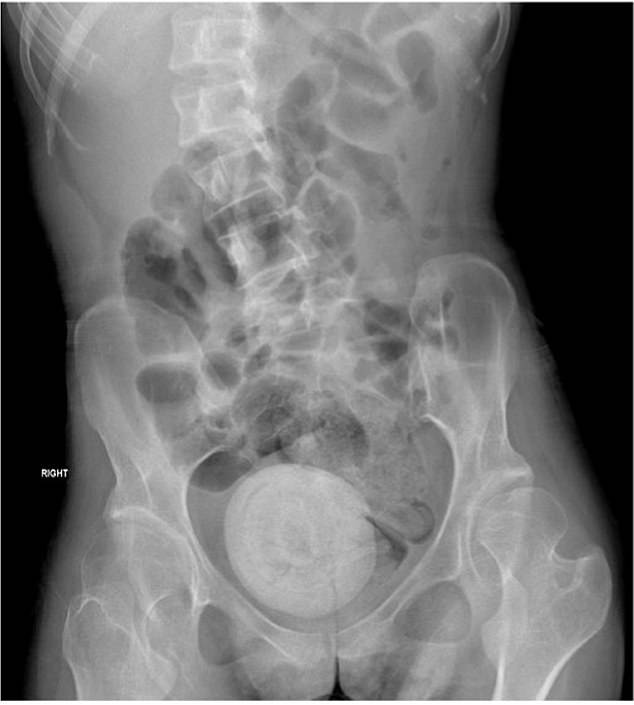

Doctors said she looked pale and lethargic. A CT scan was performed on her abdomen and pelvis, and images showed a large, round mass in her pelvic area.